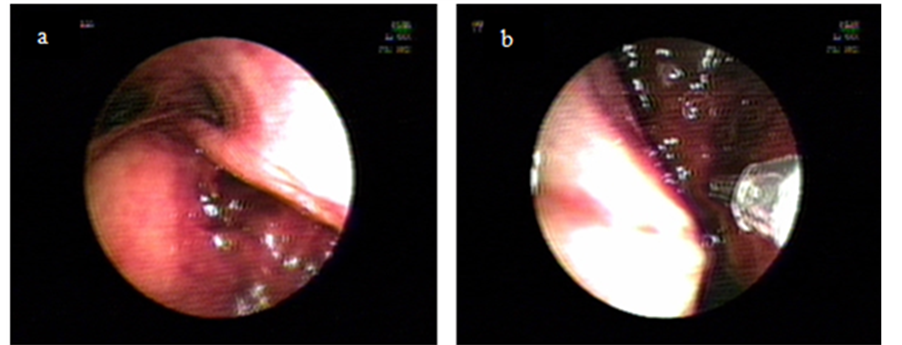

A 52 years old morbid obese lady consults at the Emergency Department of our Hospital with severe Community Acquired Pneumonia in respiratory failure with a Pa02/Fi02 ratio of 120 and obtunded, requiring immediate orotracheal intubation and connection to invasive ventilation. Tracheal intubation was difficult because of extreme obesity, shortness of neck and psychomotor agitation. Immediately after connection to a ventilator programmed with protector ventilation parameters progressive subcutaneous emphysema at the cervical region appeared. The patient evolved initially with arterial hypotension needing vasoactive drugs. The X-ray of thorax aroused the suspicion of overinflation of cuff (Figure 1) and the Computed Tomography of thorax (CT) of thorax depicted lost of continuity of the distal membranous wall of the trachea with air leak into the mediastinum (Figure 2). Bronchoscopy showed a large 4 cm rupture of the posterior wall of the trachea with protrusion of anterior wall of the esophagus into the tracheal lumen (Figure 3(a)). Broad spectrum antibiotic regime was started (ertapenem).

Due to its immediate supracarinal location, which made impossible to pass the endotracheal tube over the defect to isolate it without causing monobronchial intubation we decided to treat it locally by injecting 30 cm3 of PRP on each lip of the lesion with a double lumen catheter. Through one of the lumens we injected PRP and through the other we injected Calcium Chloride 10% in order to obtain in situ activation of platelets and therefore a faster action (Figure 3(b)). In a new CT on the next day there was no evidence of passage of air into the mediastinum. At seven days after the procedure bronchoscopy visualized a fibrin layer at the original place of wound with a scar in formation underneath (Figure 3(c)). The patient was successfully extubated; one week later CT showed a well defined scar at the intervention place and the patient was discharged (Figure 3(d)). One month away she is seen as an outpatient, doing well, with non functional or anatomic sequelae.

Figure 3. (a) Shows posterior wall of trachea tear; (b) Shows injection; (c) Shows scar after 7 days procedure (arrow); (d) Shows definite scar after 14 days of procedure (arrow).